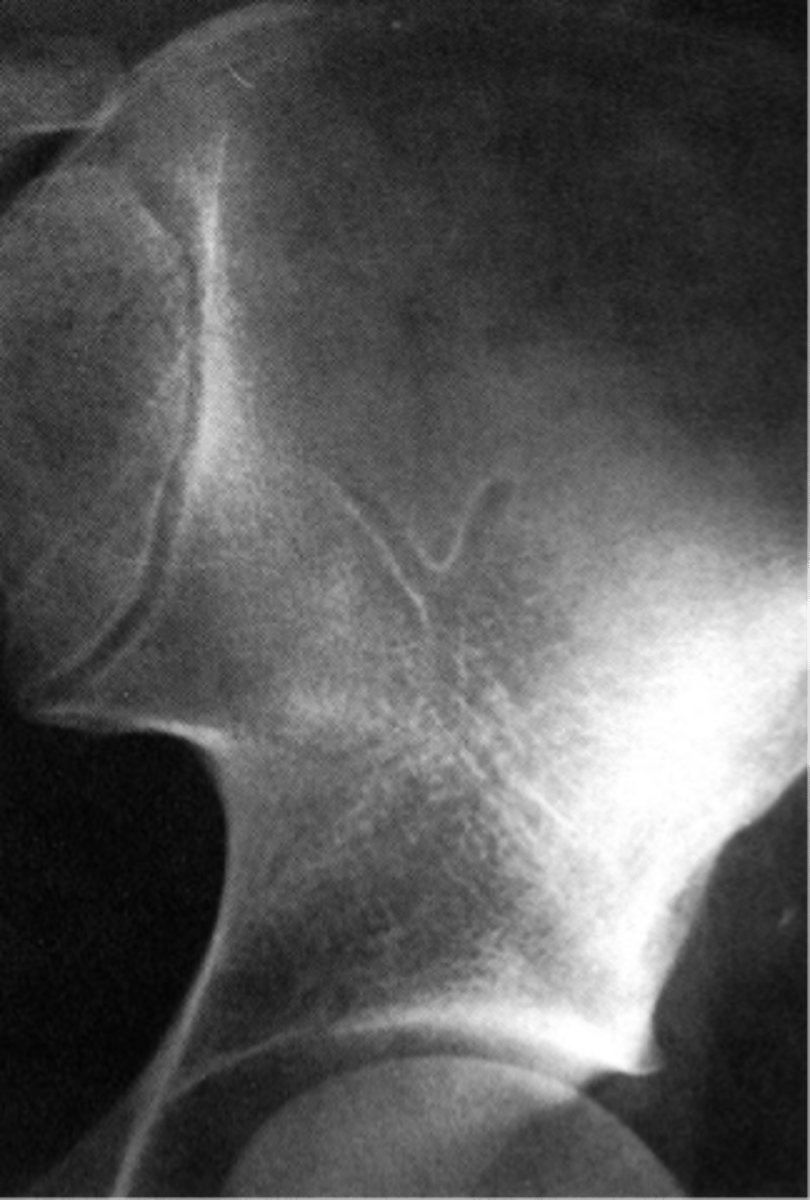

Wards triangle

An area that appears more radiolucent because it is surrounded by an abundance of trabeculae. The 1˚ and 2˚ compressive and tensile groups of the proximal femur leave a small region to appear more lucent

<p>An area that appears more radiolucent because it is surrounded by an abundance of trabeculae. The 1˚ and 2˚ compressive and tensile groups of the proximal femur leave a small region to appear more lucent</p>

New cards

Osteopenia

Wards triangle becomes enlarged as bone density reduces, signifying _____

<p>Wards triangle becomes enlarged as bone density reduces, signifying _____</p>